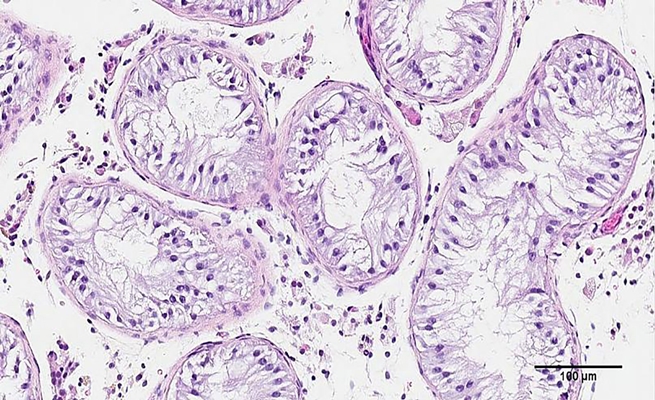

واستخدم الفريق في جامعة كولومبيا البريطانية في فانكوفر طابعة بيولوجية ثلاثية الأبعاد لإنشاء نماذج بالحجم الطبيعي للأنابيب المنوية البشرية، الهياكل الموجودة داخل الخصيتين التي تنتج الحيوانات المنوية بشكل طبيعي، بحسب “يورونيوز”.

أجرى الباحثون “خزعة”-اختبارٌ طبي يجريه جراح أو طبيب أشعة تدخّلي أو طبيب قلب تدخّلي بأخذ عينة من خلايا أو أنسجة ليتم فحصها- للخلايا الجذعية من خصيتي مريض يعاني من فقد النطاف غير الانسدادي (NOA). وتمت رعاية الخلايا حتى نموها حيث قام الباحثون بطبعتها بتقنية ثلاثية الأبعاد داخل مجسم مخصص على شكل هيكل طويل ومجوف مشابه للأنابيب المنوية التي تنتج الحيوانات المنوية عادة.

يشير الدكتور فلانيجان بقوله “نحن نطبع هذه الخلايا ثلاثية الأبعاد في بنية محددة جدًا تحاكي تشريح الإنسان، ونعتقد أنها أفضل طريقة لتحفيز إنتاج الحيوانات المنوية”.

بعد 12 يوماً من طباعة الخلايا، توصل فريق البحث إلى أن الخلايا المطبوعة والموضوعة داخل الأنابيب قد نجت. والأفضل من ذلك، فإن الخلايا المطبوعة نمت إلى العديد من الخلايا المتخصصة التي تشارك في إنتاج الحيوانات المنوية وأظهروا تحسناً كبيراً في ما يسمى بصيانة الخلايا الجذعية للحيوانات المنوية.